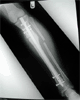

Progress

Post-op 2nd surgery :

Acute correction with IM nailing

Deformity corrected with 150degrees knee motion